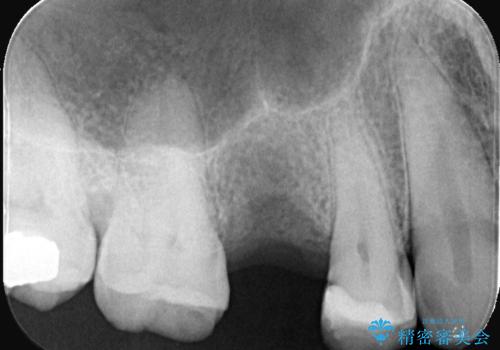

- 「歯茎にニキビみたいのが出来て歯が揺れている」を主訴に来院された患者様です。

右上5番が根尖性歯周炎と歯周病が同時に併発しており、骨が大きく溶け、歯の動揺も著しかったため保存困難と判断をし抜歯してインプラントで治療を行いました。